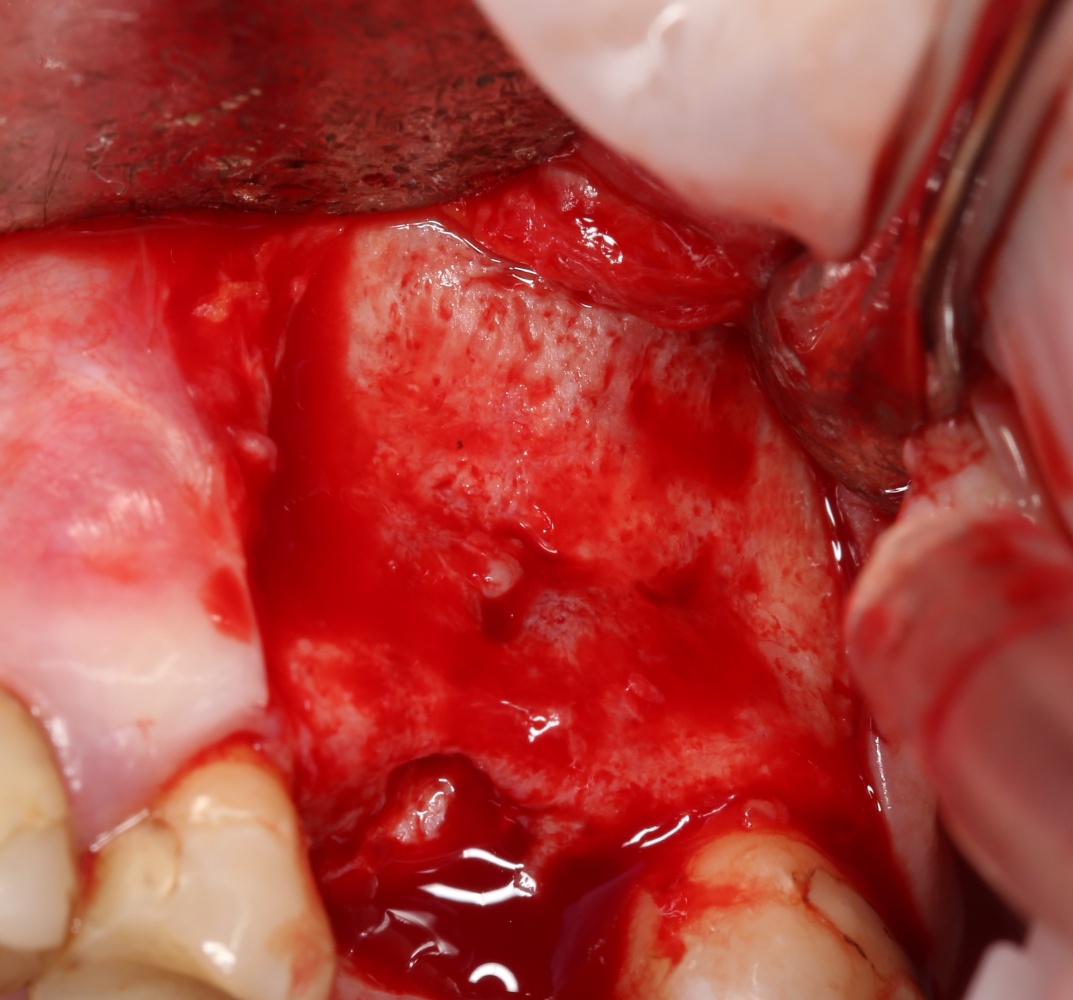

Как на фотографии выше — из-за целого ряда вмешательств и существовавшего ранее ороантрального соустья можно сказать, что от слизистой оболочки верхнечелюстной пазухи почти ничего не осталось. Можем ли мы как-то закончить эту работу? Легко:

Первая операция — мы не можем сразу поставить имплантат из-за почти полного отсутствия кости между полостью рта и дном верхнечелюстной пазухи: